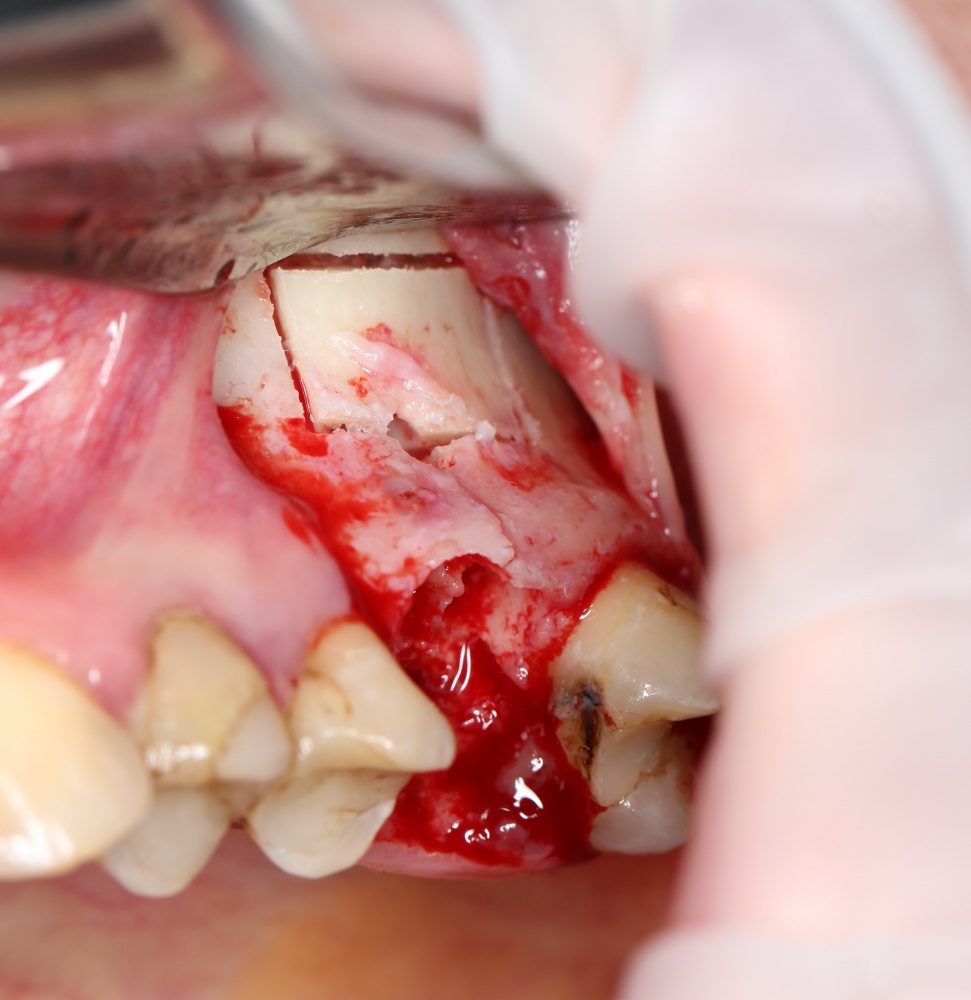

Кстати, обрати внимание на ширину альвеолярного гребня (левая картинка). Она чуть меньше 3 мм. Это объясняет, почему я засомневался в возможности установки имплантатов одновременно с остеопластикой. Понятно и без КЛКТ.

Наперво, мне нужно удалить разрушенный зуб и получить костный аутотрансплантат.

Возвращаемся к основной операционной области. Еще раз посмотрим на альвеолярный гребень, поофигеваем от его ширины и моих грандиозных планов: